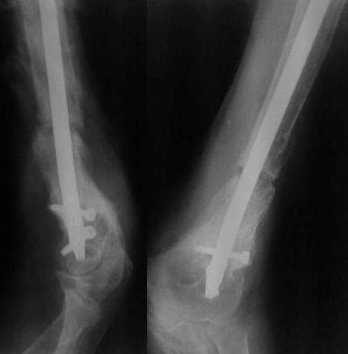

Неудачный остеосинтез пластиной: поломка винтов. После удаления сформирался гиполастический ложный сустав. Остеосинтез АВФ, циклическая компрессия-дистракция в области ложного сустава привела к формированию хорошей рентгенологической костной мозоли. Через 1,5 месяца ходил в аппарате без дополнительных средств опоры. Через 6 месяцев после клинической пробы - демотаж. Через 4 месяца после демонтажа - лизис костной мозоли, рецидив деформации.

В подобной ситуации закрытое штифтование с рассверливанием сразу после удаления пластины или, при необходимости, после восстановления оси аппаратом, имеет подавляющие шансы на успех. Вмешательство на зоне несращения не нужно.

А эти пресловутые вторичные деформации специфичны для аппаратного лечения, после шитфтования этой проблемы нет.